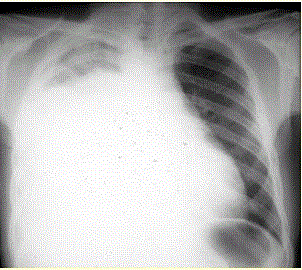

问题  患者男,34岁。进行性胸闷、气促1个月余,伴有干咳、右胸隐痛以及消瘦,无咯血、发热、盗汗、潮热等。 为进一步明确病因诊断,应选择的检查是(提示 患者既往有“慢性胃炎”史10年,未详细检查过,近半年有上腹隐痛、食欲减退、体重减轻。无吸烟及酗酒史,否认肝炎、肺结核病史。)

选项 A、超声心动图检查 B、血清ANA、抗dsDNA抗体、抗Sm抗体检测 C、胸腔积液细菌培养 D、PPD皮试 E、肺功能检查 F、心电图检查 G、胸部CT检查 H、胸腔积液沉淀找癌细胞 I、胸腔积液沉淀找抗酸杆菌 J、胃镜检查 K、胸膜活检病理检查 L、痰找抗酸杆菌检查

答案 GHJK